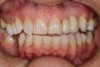

Fig 3. Tooth No. 28 had a Class V filling that failed with recurrent decay (Fig 3). A tuberosity CTG with a 1.5 mm thickness was placed, and after 1 year there was no keloid-like appearance (Fig 4).

Figure 3

Class V fillings are artificial materials that tend to fail at the apical extent and have poor long-term success (Figure 3).1 Conversely, CTGs are natural and attach to the root surface and have high long-term success (Figure 4).1

Regarding the avoidance of a gingivoplasty procedure later, there appears to be nothing in the literature describing the ideal thickness of a tuberosity CTG. From palatal and allograft thickness recommendations, one could hypothesize that the thickness be between 0.75 mm and 2 mm. This article will propose a graft thickness between 1 mm to 1.5 mm (Figure 3 and Figure 4) for the optimal functional and esthetic outcome and will discuss various procurement and fileting techniques.